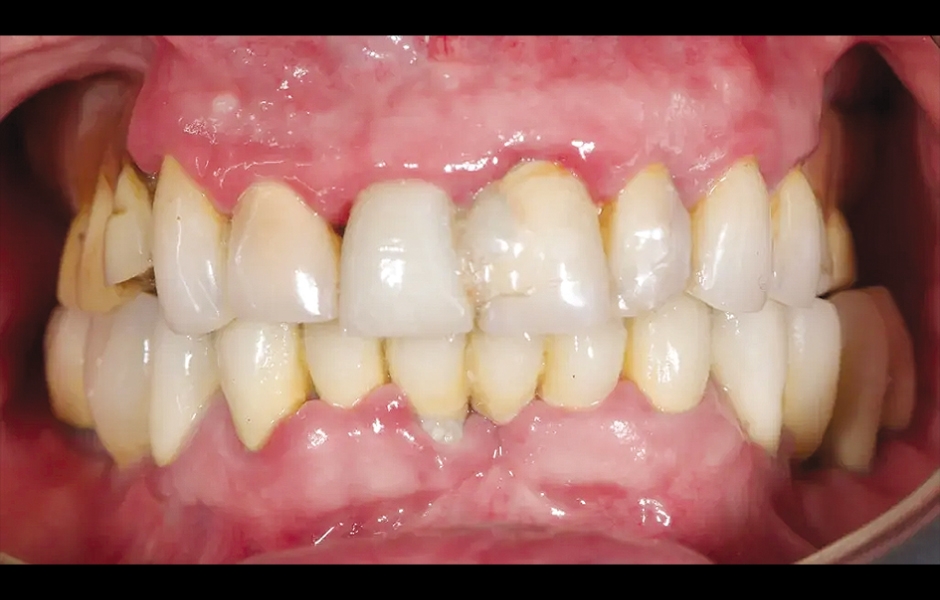

85letý částečně bezzubý pacient byl odeslán na naši kliniku k celkové rehabilitaci horní čelisti. Pacient byl v dobrém celkovém zdravotním stavu a nekuřák. Jeho hlavní stížnosti zahrnovaly obtíže při žvýkání, bolest v horní čelisti a občasný zápach z úst. Klinické a radiologické vyšetření odhalilo krátký fixní metalokeramický můstek nesený sedmi frontálními zuby horní čelisti. Protetická práce se uvolnila a čtyři z pilířových zubů byly strukturálně narušeny. Zbývající tři vykazovaly různé stupně kazivých lézí a parodontálních problémů. Byla stanovena diagnóza selhávající dentice (obr. 1 a 2).

Obr. 1: Výchozí situace, čelní pohled. (Všechny snímky: Dr. Marco Tallarico a kol.).